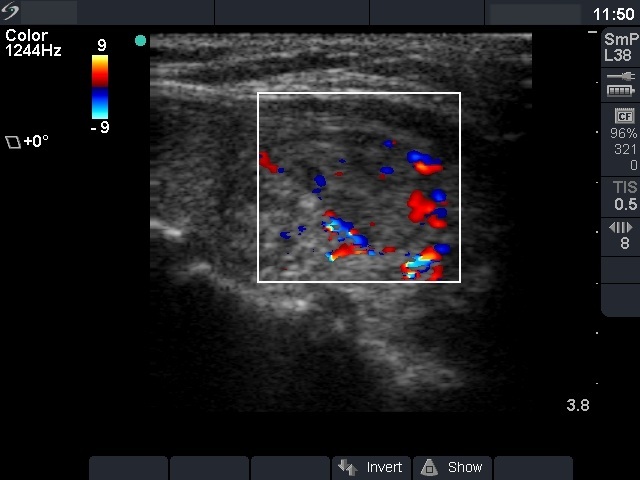

Benign nodular hyperplasia - Case 40. (ultrasonographic picture 5)

Right lobe, longitudinal scan

Other section of the left lobe, longitudinal scan, color Doppler mode. Both peri- and intranodular blood flow can be seen.